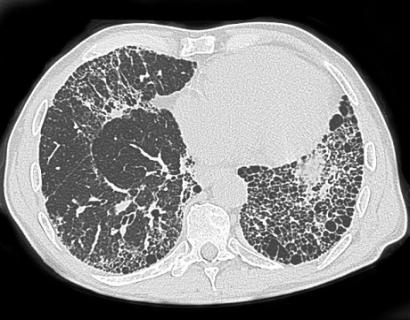

La fibrosis pulmonar es una afección, potencialmente aguda, que impide la llegada de suficiente oxígeno a los pulmones y a la sangre. Entre las causas potenciales que provocan su aparición se encuentra la neumonía, una complicación que incluso puede aparecer en casos que no evolucionan al estado de gravedad por SARS-CoV-2.

Los pacientes que desarrollan SDRA también se enfrentan a la aparición de otras dificultades. Algunas de ellas son la aparición de insuficiencia de múltiples sistemas de órganos, neumotórax — complicación asociada frecuentemente a la ventilación mecánica — y fibrosis pulmonar.

Los pocos estudios realizados a pacientes que sobrepasan la Covid-19 y presentan fibrosis posterior al síndrome de dificultad respiratoria aguda, sugieren que la dificultad no es progresiva. Esto significa que la cicatrización no continúa con el tiempo. No obstante, es cierto que su recuperación es larga, ya que, en los enfermos más complicados, puede durar aproximadamente un año. Y aunque puede haber casos graves y discapacitantes, generalmente los pacientes logran sobrepasar la dificultad sin complicaciones.

Muchos de ellos han confundido la fibrosis pulmonar idiopática con la Enfermedad pulmonar intersticial (EPI). Según la Sociedad Estadounidense del Pulmón, este término abarca un gran grupo de enfermedades que causan cicatrización en los pulmones y, al igual que la idiopática, provoca rigidez en esos órganos, lo cual dificulta la respiración y el suministro de oxígeno al torrente sanguíneo.

La mayor parte del tiempo esta afección es irreversible y empeora tanto con el tiempo, que muchos casos requieren trasplantes como solución definitiva a esta afección.

De acuerdo con declaraciones de la Fundación contra la Fibrosis Pulmonar, las características de la fibrosis presentada por pacientes que sufrieron SDRA luego de contraer Covid-19 son distintas a las de aquellos que presentan los pacientes con EPI. Por ello, es imprescindible no confundirlas.